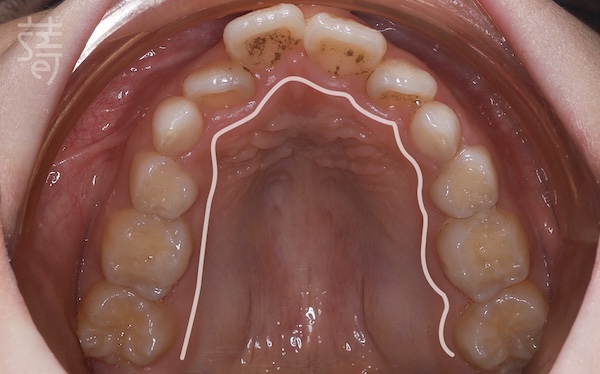

檢查後發現,小緹的牙弓偏窄、牙齒擁擠,門牙稍往前,加上她習慣用錯誤的方式呼吸,這些都會讓狀況逐漸惡化。

Dr. Ko found that Ti’s dental arch was narrow, her front teeth slightly protruded, and her breathing habits weren’t helping—issues that would likely worsen over time.

不過柯醫師也向媽媽解釋,這類狀況在齒列混合期孩子身上很常見,小緹正處在「第一階段矯正期」,也就是7~10 歲、乳牙和恆牙同時存在的階段。這時顎骨正快速發育,是早期介入的黃金時間,只要妥善接受治療,不僅能引導恆牙長在較理想的位置,也能降低未來需要大規模矯正的可能。

He explained that this is common in the mixed-dentition stage, when ages 7 to 10 offer a rare window: the jaw is still developing, and early orthodontic guidance can shape where adult teeth erupt and reduce the need for major treatment later on.

為了從根本改善,小緹接受齒性擴弓,慢慢把上顎調回理想的卵圓形,預留空間給未來的恆牙。同時,柯醫師也建議媽媽帶她做耳鼻喉科檢查,讓呼吸與口腔同步調整。

To address the root cause, Ti began a gentle dental expansion to guide her upper arch back toward a healthy, oval shape, creating room for her future permanent teeth. Dr. Ko also encouraged her mother to visit an ENT specialist, ensuring Ti’s breathing and oral development could progress together.